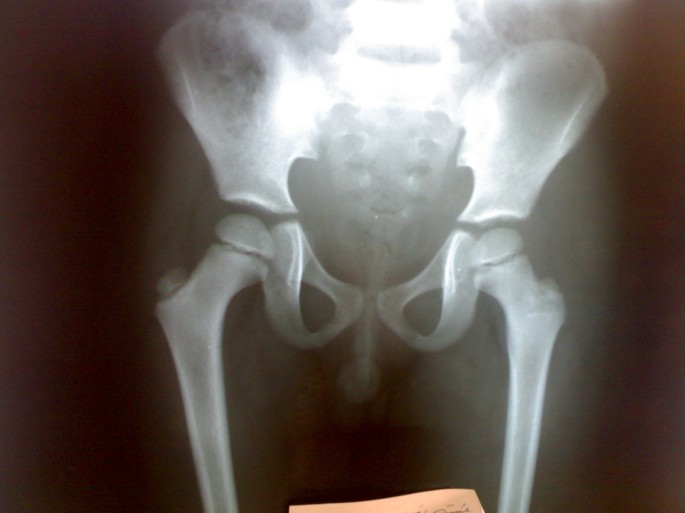

Plain x ray of both hips and thigh revealed soft tissue edema of left thigh and normal left hip joint, figure 2. Chest radiograph was normal. Doppler ultrasonographic examination of the left lower extremity revealed no abnormality. MRI of the left thigh revealed extension of inflammation along the fascial plains, figures 3.